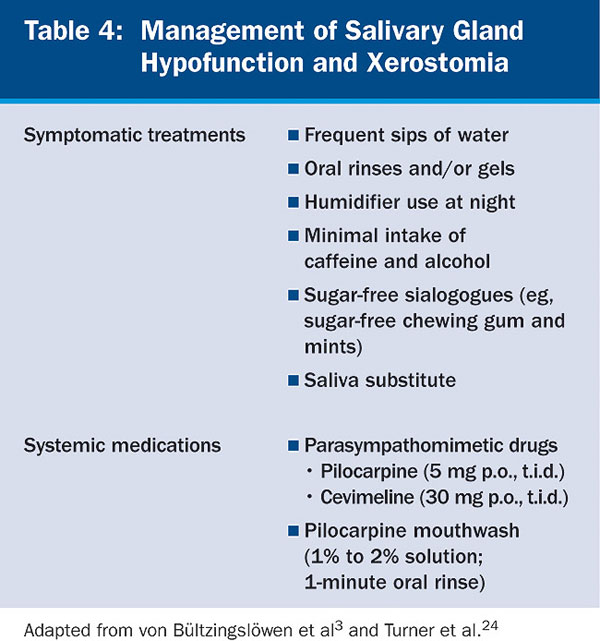

After determining a diagnosis and possible underlying causes, dental clinicians should begin management of these patients according to the severity of the condition. Symptomatic or palliative treatment of xerostomia, although transient, has proven to be beneficial and patient compliance is good (Table 4). Frequent sips of water as well as alcohol-free oral rinses, gels, mouthwashes, sugar-free chewing gum, and mints have all proven useful in reducing the feeling of dry mouth. Because xerostomia typically feels worse at night, use of a humidifier at night is helpful. Avoiding dehydration by minimizing caffeine and alcohol intake is recommended. Artificial saliva is typically not well-liked by patients and does not last.24 Severe salivary gland hypofunction and associated xerostomia can be managed by generalized parasympathomimetics, such as pilocarpine HCI (SALAGEN®, Eisai, www.eisai.com). However, the side effects of that medication, such as sweating, vasodilation, headaches, and urinary frequency, can decrease patient compliance.25 Cevimeline HCI (EVOXAC®, Daiichi Sankyo Inc., www.daiichius.com) is another drug approved by the Food and Drug Administration (FDA) for treatment of oral dryness in Sjögren’s syndrome and administered as 30 mg, p.o., t.i.d.3,26 Pilocarpine HCI has been shown to be effective when used as a mouthwash for 1 minute in healthy individuals. This has shown to increase objective salivary flow (with 1% and 2% concentrations) and subjective salivary flow (with 2% concentration).27 Amifostine (Ethyol®, MedImmune, www.medimmune.com) is effective in patients receiving radiotherapy.28 Amifostine is a thiol drug that is cytoprotective by several mechanisms, including scavenging oxygen-derived free radicals, deoxyribonucleic acid protection and repair acceleration, and induction of cellular hypoxia. The medication has FDA approval to reduce the incidence of moderate-to-severe xerostomia in patients undergoing postoperative radiation treatment for head and neck cancer.29-31